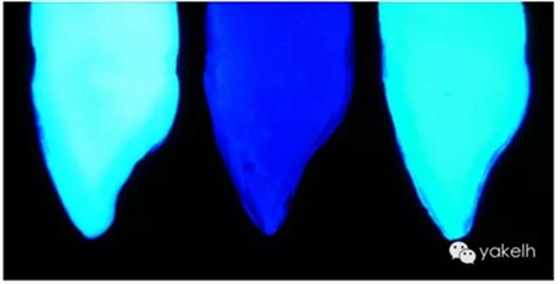

圖2.32天然牙和復合樹脂制作的牙齒在紫外線光下拍攝的影像。

圖2.33天然牙、無熒光復合樹脂牙和熒光復合樹脂牙切片在紫外線下的影像。